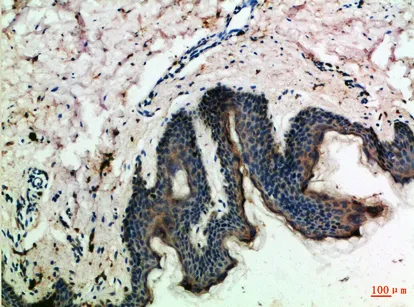

IL-17C Rabbit Polyclonal Antibody

Cat: APRab12506